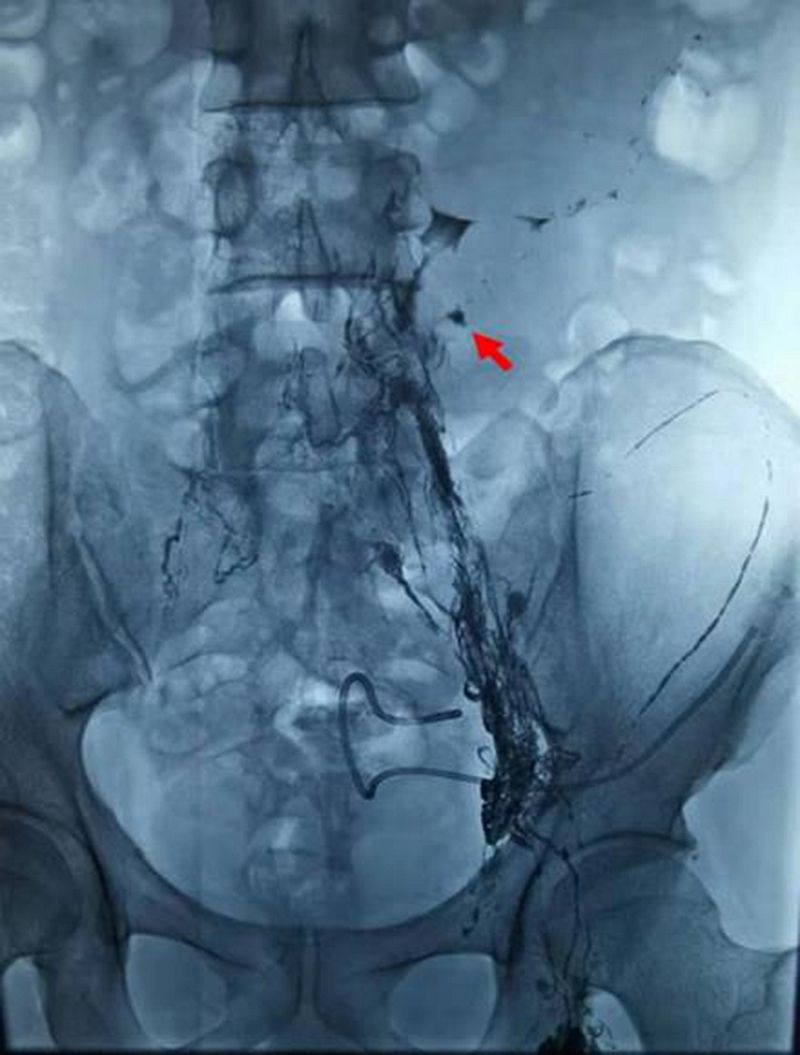

淋巴结造影找到破裂口(红色箭头 )

面对这样的情况,中国医学科学院肿瘤医院深圳医院立即组织开展多学科讨论,决定通过介入微创的方法来治疗顽固性淋巴漏。经过多学科充分的讨论与严谨的评估,介入治疗科副主任宋鹏为刘先生制定了严密的手术计划和诊疗方案——超声引导下穿刺腹股沟淋巴结,然后进行淋巴造影,造影确定漏口后进行淋巴漏的栓塞。

2021年6月9日,在介入治疗科副主任宋鹏和超声科医生的密切配合下,刘先生的左侧腹股沟淋巴结被成功穿刺,连接注射器缓慢注射造影剂,通过每间隔3-5分钟摄影,大约1小时左右淋巴管破口也被顺利地找到。在宋鹏主任的精细操作下,一根纤纤细针穿过刘先生的腹腔,精准穿刺到漏口部位,随着微导管对缺口位置再次确认及生物胶的缓缓注入,淋巴管的破口被成功封堵,手术取得了圆满成功。